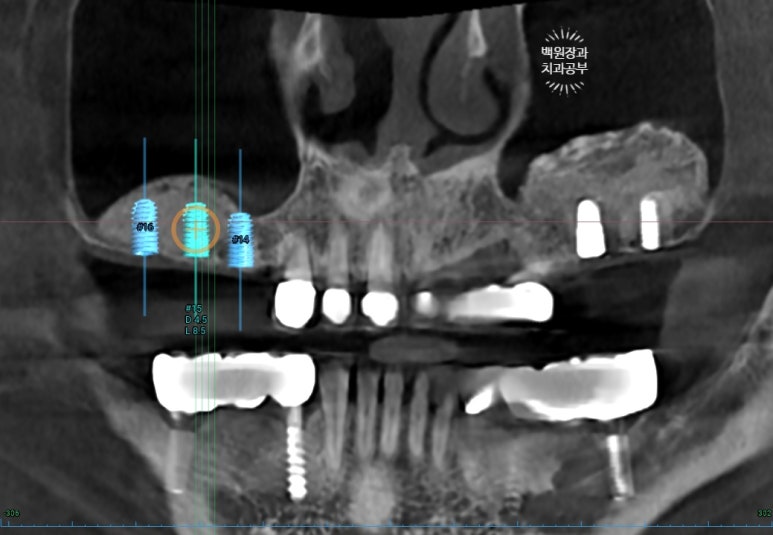

다음 순서는 오른쪽 어금니 임플란트를 심을 차례입니다.

수술 전 찍은 치과용 CBCT에서 임플란트를 모의로 배치해봅니다.

왼쪽 어금니 임플란트는 잘 되어있는 것을 보실 수 있고, 이제 오른쪽 임플란트도 예쁘게 잘 심으면 됩니다.

생각보다 임플란트 3개를 나란히 보이도록 심는게 쉽지는 않습니다만.. 집중 또 집중!!